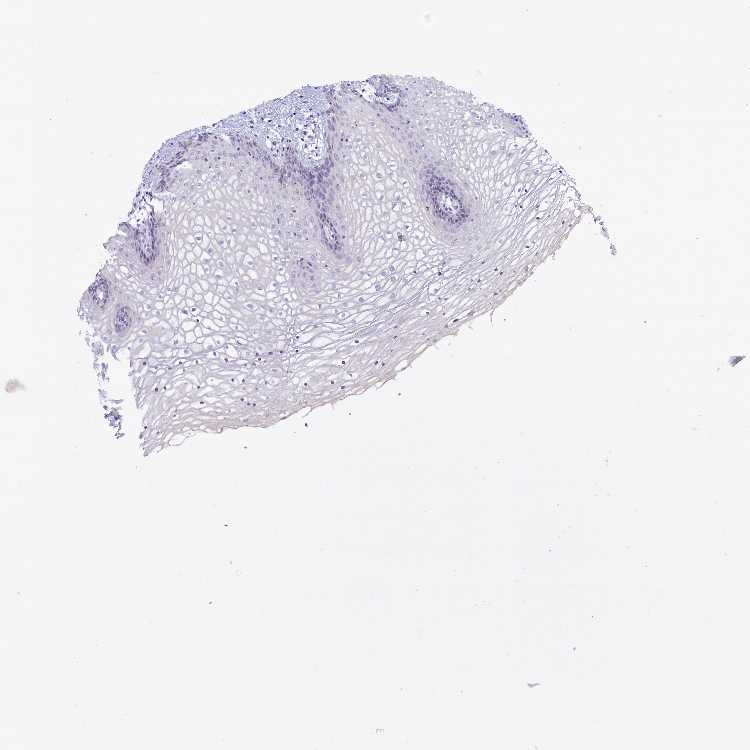

TISSUE PRIMARY DATA VAGINA Show tissue menu

VAGINA - Antibody stainingi

Antibody staining in the annotated cell types in the current human tissue is reported as not detected, low, medium, or high, based on conventional immunohistochemistry profiling in selected tissues. This score is based on the combination of the staining intensity and fraction of stained cells.

Each image is clickable and will lead to virtual microscopy that enables deeper exploration of all samples and also displays staining intensity scores, fraction scores and subcellular localization as well as patient and tissue information for each sample.

Antibody HPA041343Antibody HPA041967

Squamous epithelial cells Not detectedLow